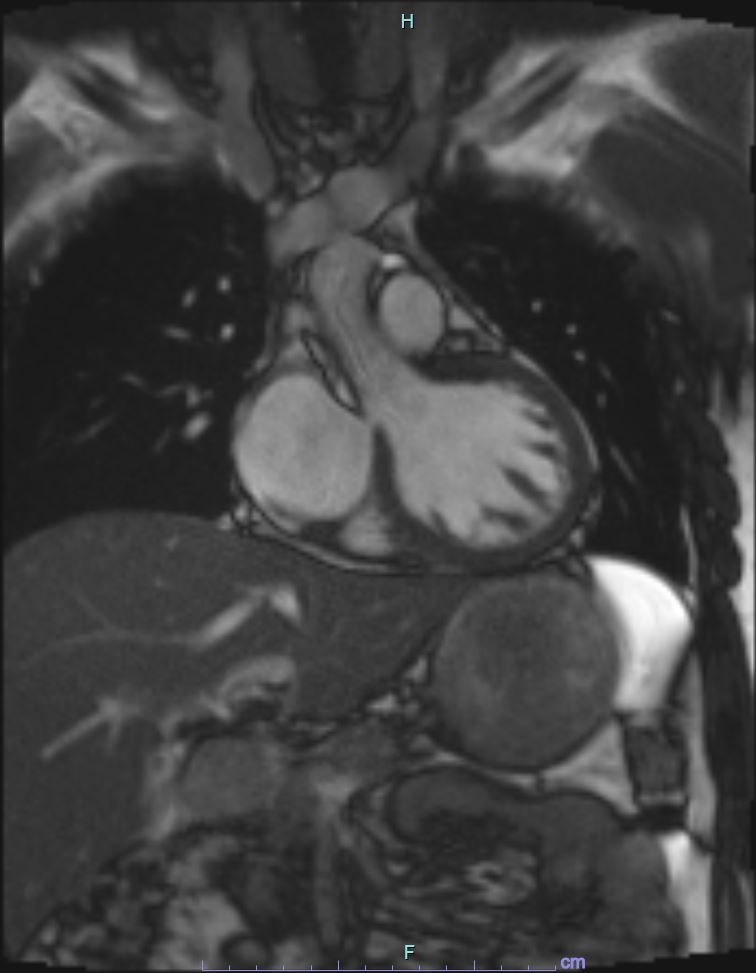

Echocardiogram : LVEF 59%, no regional wallmotion abnormalities. No dissection flap at the aortic root .

Further history revealed that he had brief flulike symptoms prior to onset of chest pain. He added he also recently consumed ¡®Honey¡¯ that he purchased from social media- Tik Tok. Further investigation revealed that there the purchased botanical honey contained kratom in its ingredient. Blood investigation showed rise of creatinine kinase from 562 U/l to 583 U/l as well as troponin T from 762 pg/ml to 875 pg/ml. Due to the nature of his diagnosis of MINOCA, a cardiac MRI was done, however showed absence of myocardial inflammation, edema, fibrosis or infiltration.